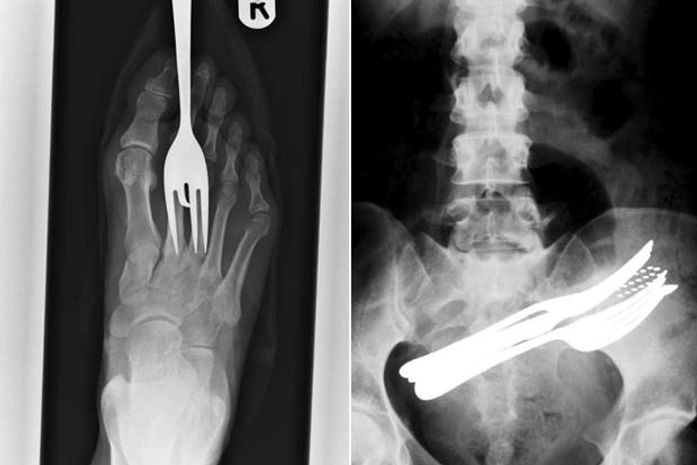

No início do mês, um prisioneiro do Sri Lanka que tentou esconder seu telefone celular durante uma inspeção em sua cela foi descoberto quando os guardas ouviram toques vindos de suas nádegas. O condenado de 58 anos precisou ser internado no hospital, onde os médicos retiraram o aparelho de seu reto. Abaixo, o G1 reúne esse e outros raios-X bizarros.

Bizarro